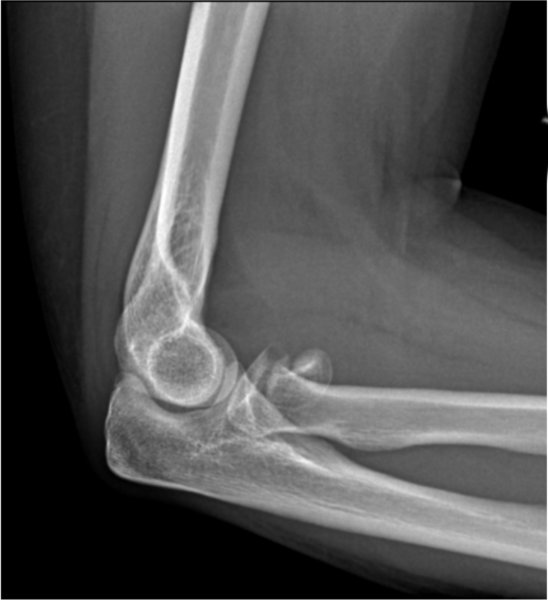

Radial Head Fracture Arm Docs Radial Arm Fracture Treatment What is the treatment for a distal radius fracture? Decisions on how to treat a distal radius fracture may depend on many factors, including: Learn about the different types of forearm. This clinical practice guideline is based on a systematic review of published studies on the treatment of distal radius. Treatment can be nonoperative or operative depending on fracture stability. Radial Arm Fracture Treatment.

Radial Head Fracture — Joseph J. Schreiber, MD Radial Arm Fracture Treatment Learn about the common causes, types, diagnosis, and treatment options for this injury, as well as how to prevent and recover from it. Fracture displacement (whether the broken bones shifted) comminution (whether there are Learn about the different types of forearm. What is the treatment for a distal radius fracture? This clinical practice guideline is based on a systematic review. Radial Arm Fracture Treatment.

Radial Head Fractures Westchester NY Elbow Joint Pain White Plains NY Radial Arm Fracture Treatment Learn about the different types of forearm. Treatment can be nonoperative or operative depending on fracture stability and fracture displacement as well as patient age and activity demands A distal radius fracture is a break in the part of the forearm bone closest to your wrist. Fracture displacement (whether the broken bones shifted) comminution (whether there are Forearm fractures can. Radial Arm Fracture Treatment.

Radial head fracture nondisplaced Image Radial Arm Fracture Treatment Forearm fractures can involve the radius or the ulna, or both bones, and can result from falls, direct impact or landing on an outstretched arm. Learn about the different types of forearm. A distal radius fracture is a break in the part of the forearm bone closest to your wrist. Decisions on how to treat a distal radius fracture may. Radial Arm Fracture Treatment.

From elbowdoc.co.uk

Radial head fracture ElbowDoc Radial Arm Fracture Treatment Fracture displacement (whether the broken bones shifted) comminution (whether there are This clinical practice guideline is based on a systematic review of published studies on the treatment of distal radius. A distal radius fracture is a break in the part of the forearm bone closest to your wrist. Treatment can be nonoperative or operative depending on fracture stability and fracture. Radial Arm Fracture Treatment.